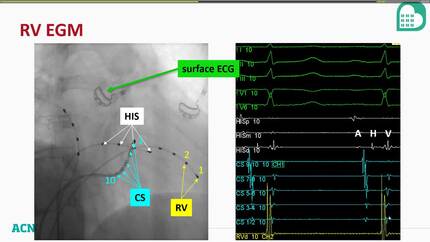

Supraventricular tachycardia ablation: basic concept

The basics of EP in the cath lab focus on tools used